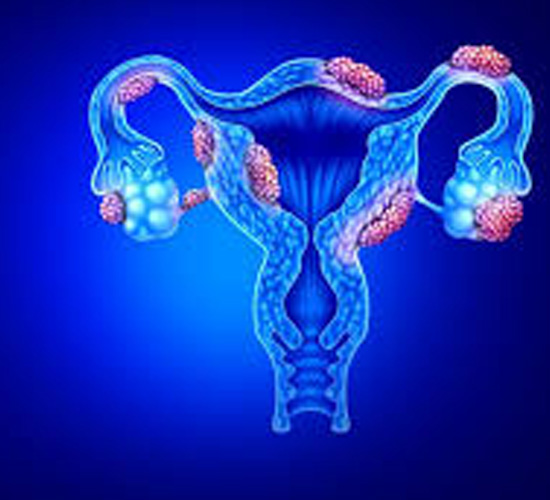

Uterine Fibroids Treatment

We offer advanced treatments for uterine fibroids, relieving symptoms and improving fertility through medication, minimally invasive procedures, or surgery.

Endometriosis Treatment

Specialized endometriosis treatments help manage pain, improve fertility, and restore reproductive health through medication, surgery, or hormonal therapy.